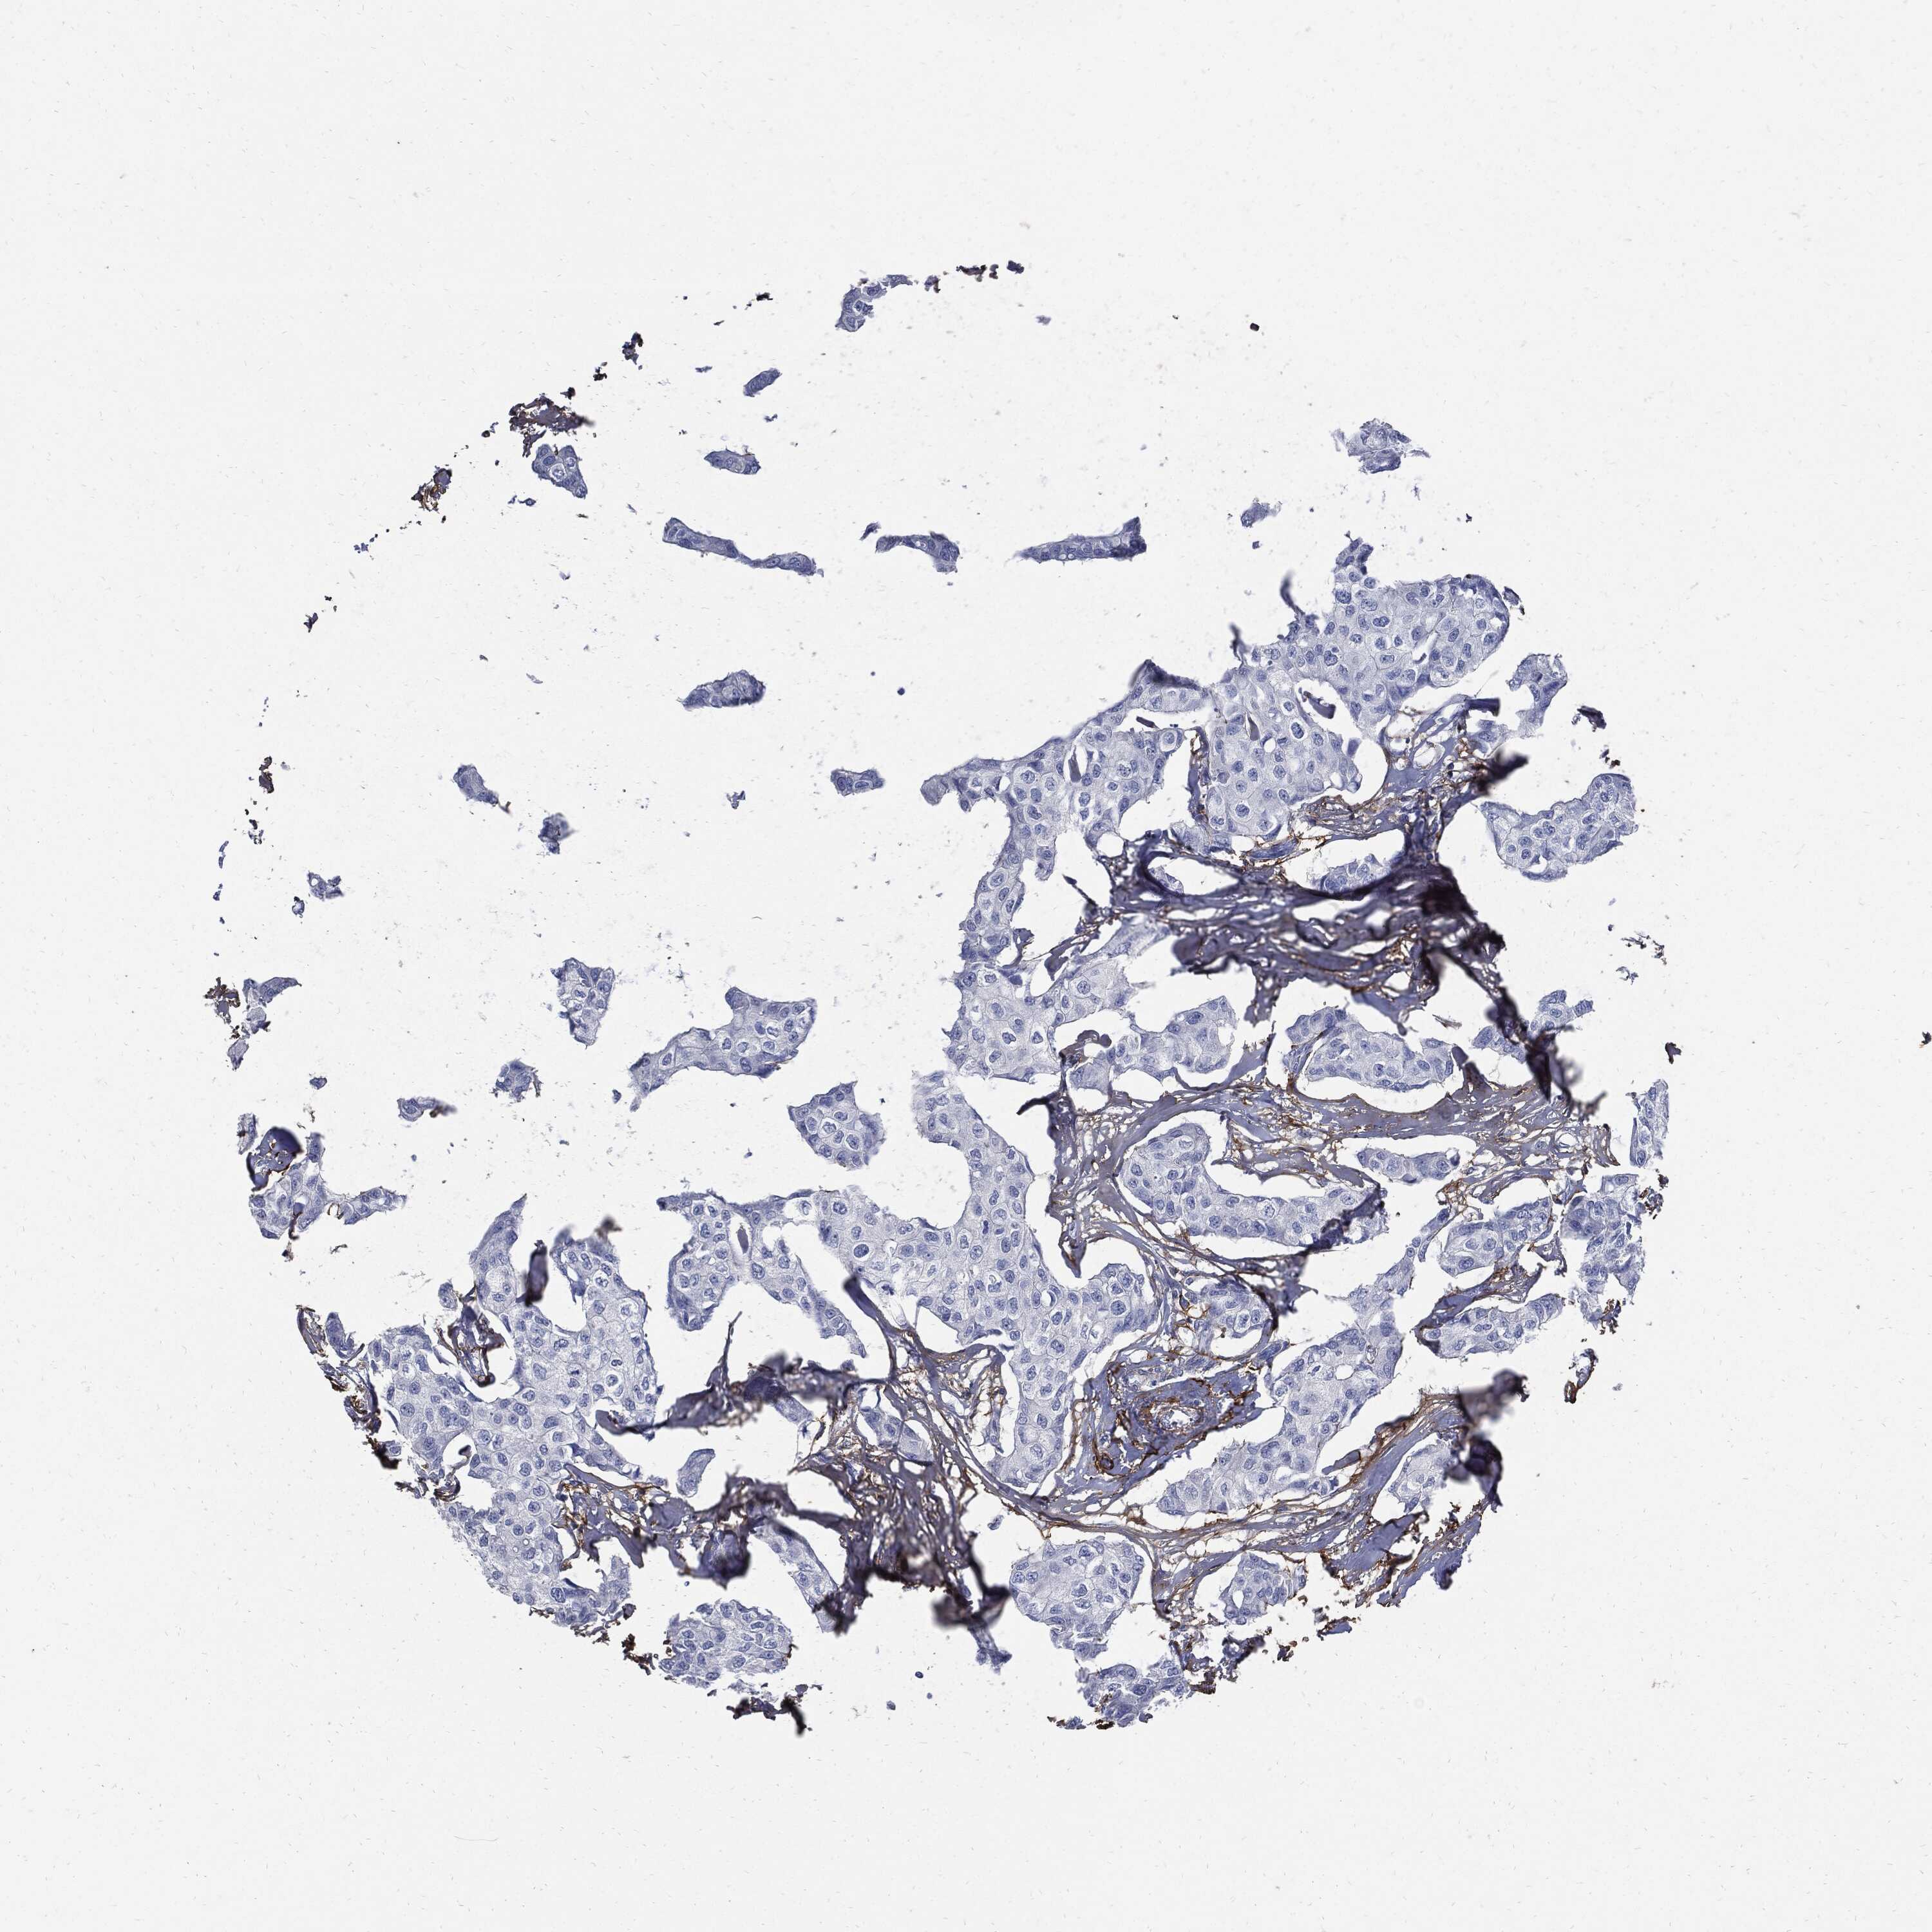

BRCA TCGA BRCA VALIDATION PROTEIN EXPRESSION

ANTIBODIES

AND

VALIDATION